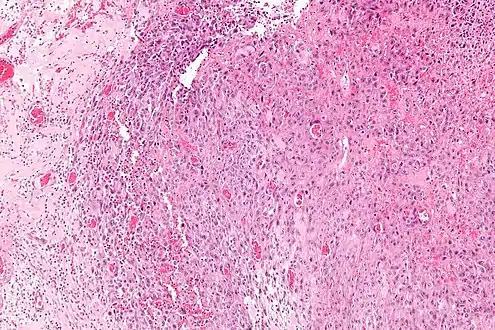

| Micrograph of an epithelioid sarcoma. H&E stain. | |

Histologically, epithelioid sarcoma forms nodules with central necrosis surrounded by bland, polygonal cells with eosinophilic cytoplasm and peripheral spindling.[3] Epithelioid sarcomas typically express vimentin, cytokeratins, epithelial membrane antigen, and CD34, whereas they are usually negative for S100, desmin, and FLI1 (FLI-1).[3] They typically stain positive for CA125.[4]

Intermed. mag.